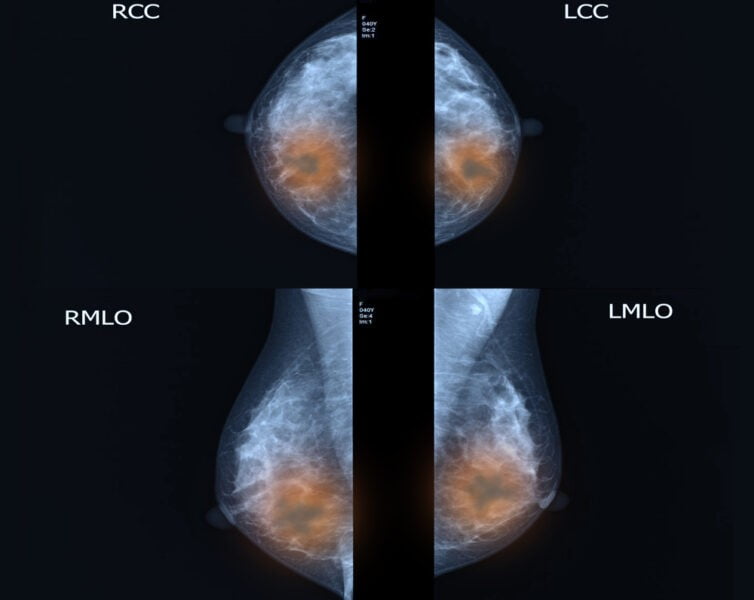

Mammogram: Ini adalah tes pencitraan. Wanita di atas 40 tahun mungkin dianjurkan untuk menjalani mammogram jika mereka memiliki kecenderungan genetik kanker payudara.